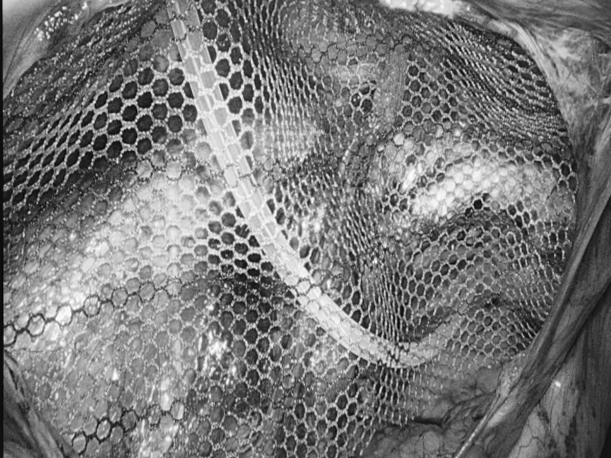

为深入践行人才强院核心战略,加速打造高水平医疗专家团队,引领学科跨越式发展,7月15日,贵州航天医院成功签约(柔性引进)知名肛肠外科专家高大勇教授,并举行“高大勇教授名医工作室”授牌仪式。贵州航天医院党委书记杨军,院长廖江荣,副院长彭亮、马庆庆、蒋婷出席仪式,普外科全体医护人员参加。 仪式上,杨军为高教授颁发了聘书,双方共同签署了合作协议,高教授授予普外科“名医工作室”函牌。 聘书颁发 柔性人才引进协议签约 名医工作室授牌 仪式后,高大勇教授前往科室开展早交班、教学查房等工作,针对疑难病例给予专业的治疗建议和科学指导。 此次柔性引进高大勇教授并设立名医工作室,将进一步促进贵州航天医院普外科在学科建设、技术创新、人才培养、科研教学等方面能力的提升,推动我院肛肠疾病诊疗能力实现跨越式发展,为广大患者带来优质医疗服务。 贵州航天医院普外科专家团队 高大勇 普外科(肛肠外科)学科带头人、名誉主任,主任医师、教授 临床擅长:对中西医结合诊治肛肠学科各种常见病、多发病及疑难杂症等具有丰富的临床经验。 原遵义市第一人民医院(遵义医科大学第三附属医院)、遵义市中医院肛肠科主任。中华中医药学会肛肠分会常委,全国中医肛肠学科名专家,中国健康促进与教育协会肛肠分会常委,中国康复医学会肛肠疾病康复专业委员会常委,中国民间中医医药研究开发协会肛肠分会副秘书长,中国医师协会中西医结合肛肠医师专业委员会常委,国家二级心理咨询师,贵州省第一批中医名医工作指导老师,遵义市名中医,遵义市肛肠学会会长,遵义市肛肠质控中心名誉主任,遵义市中西医结合学会名誉会长,遵义市健康科普专家,原贵州省中西医结合学会肛肠分会副主任委员、贵州省中医肛肠质控中心副主任、遵义市医学会医疗鉴定委员会专家、遵义市卫生系列高评委。发表论文30余篇,主编和参编医学著作5本,主持省级科研课题2项、市级科研课题2项、院级科研课题1项。 梁 跃 中共党员,普外科党支部书记、主任,主任医师 临床擅长:对普外科各类肿瘤手术具有丰富的临床经验。 毕业于遵义医学院,遵义市医学会小儿外科学分会常务委员,遵义市肛肠协会理事,遵义市医学会核医学分会(第二届)委员会委员;荣获第三期“黔医人才计划”优秀学员称号;主持市级课题1项,完成省级课题1项,在国内各类刊物上发表论文10余篇。 钱科洪 民盟盟员,普外科副主任医师 临床擅长:从事普外科临床工作30余年,对各类普外科疾病的诊治,乳腺、甲状腺、胃十二指肠、结直肠等疾病及疑难杂症诊治具有丰富的临床经验。 毕业于遵义医学院临床医疗系,2009年前往中山大学附属第一医院微创外科进修学习,在国内各专业期刊发表论文数篇。 贵州航天医院普外科简介 基本情况 贵州航天医院普外科成立于1968年,前身属于航天部O61基地3417医院外一科,1998年3417医院、3427医院合并后更名为普外科,下设胃肠外科、肛肠外科2个亚专业科室,拥有在全市较为先进的专科设备和技术,是中国疝病专科联盟单位,贵州医科大学附属医院胃肠外科专科联盟单位。开放床位40张,配备医护人员21人。 专科特色 普外科致力于胃肠及肛肠疾病的外科临床诊治及科研,以腹腔镜微创外科技术为本,形成以快速康复治疗胃肿瘤、结直肠肿瘤、小肠肿瘤、直肠脱垂、肥胖病、急腹症、各类疝、痔、瘘等专科特色,同时注重胃肠疾病尤其是结直肠恶性肿瘤的基础研究和临床转化研究,总体诊断和治疗水平在区域同级医院居于领先水平。 开展手术:腹腔镜下胃癌根治术,腹腔镜下袖状胃切除术,腹腔镜下胃肠道间质瘤切除术,腹腔镜下结、直肠癌根治术,胃癌、结直肠癌的精准治疗,腹腔镜下小儿疝气、成人疝修补术,腹腔镜下阑尾手术,内痔的硬化注射治疗及痔疮的微创治疗:ATH、PPH、TST,直肠脱垂的各种手术治疗,难治性伤口VSD技术,鼻胃肠管、肠梗阻导管置入术,肛肠术后间歇性导尿技术,并引进了中医适宜技术,也为各种化疗患者提供输液港安装,提高患者就医体验。 腹腔镜下腹股沟 疝无张力 修补术 腹股沟疝里金 斯坦(Lichten stein)手术 PPH微创术治疗环状混合痔 黏连性或炎性肠梗阻-肠梗阻导管 腹腔镜袖状胃切除 腹腔镜阑尾切除术 腹腔镜阑尾肿瘤切除术 腹腔镜下结肠癌根治术 诊疗范围 胃肿瘤、结直肠肿瘤、小肠肿瘤、肥胖症、各类急腹症、腹部外伤、腹壁疝、便秘、直肠脱垂、痔疮、肛瘘、肛裂等胃肠、肛肠外科疾病。 END